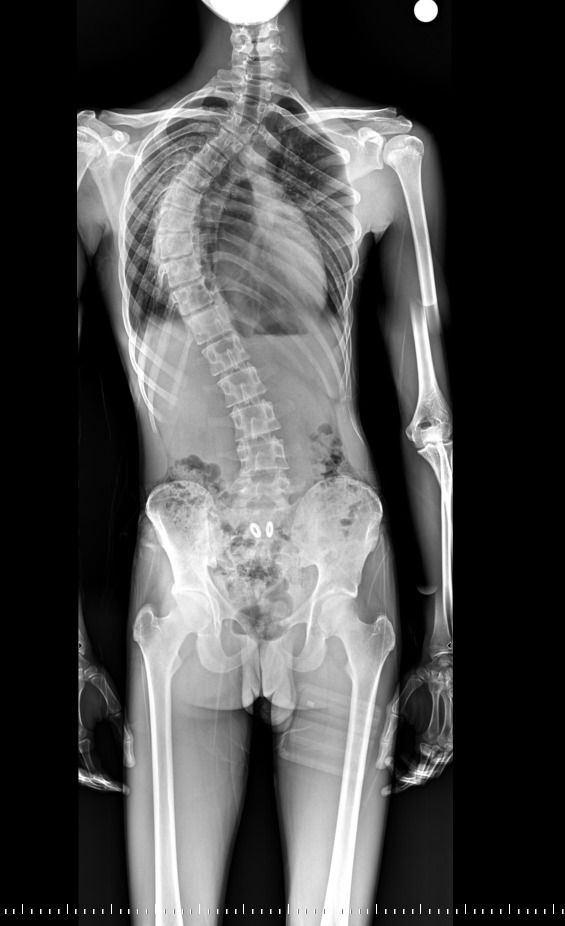

Mersin’in çarşı merkezinde hizmet veren tek devlet hastanesi olan Toros Devlet Hastanesi, sağlık alanında önemli bir başarıya daha imza attı. Kilis’te yaşayan ve ileri derece omurga eğriliği (skolyoz), kamburlaşma ile solunum sıkıntısı yaşayan 18 yaşındaki hasta, birçok merkezde gerçekleştirilemeyen zorlu ameliyat sayesinde sağlığına kavuştu.

Yapılan muayene ve ileri tetkikler sonucunda hastaya ileri derecede skolyoz tanısı konuldu. Yaklaşık dört yıldır fizik tedavi gören hastada, omurga eğriliğinin ilerlemesi durdurulamayınca solunum problemleri de ciddi boyutlara ulaştı. Bunun üzerine cerrahi müdahale kararı alındı.

İl dışından hastanemize başvuran hastamızın skolyozu yaklaşık dört yıl önce tespit edilmişti. Bu süre boyunca düzenli fizik tedavi görmesine rağmen eğrilik ilerlemiş ve ciddi solunum problemleri ortaya çıkmıştı. Yaklaşık 10 saat süren başarılı cerrahi müdahale ile omurga eğriliği düzeltildi.

Ameliyat sonrası hastamızın boyu yaklaşık 4 santimetre uzadı, solunum fonksiyonlarında belirgin düzelme sağlandı. Hastamız, ameliyattan 10 gün sonra şifa ile taburcu edildi.